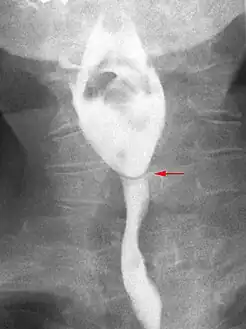

- Esophageal web stenosis in barium swallow examination frontal view.